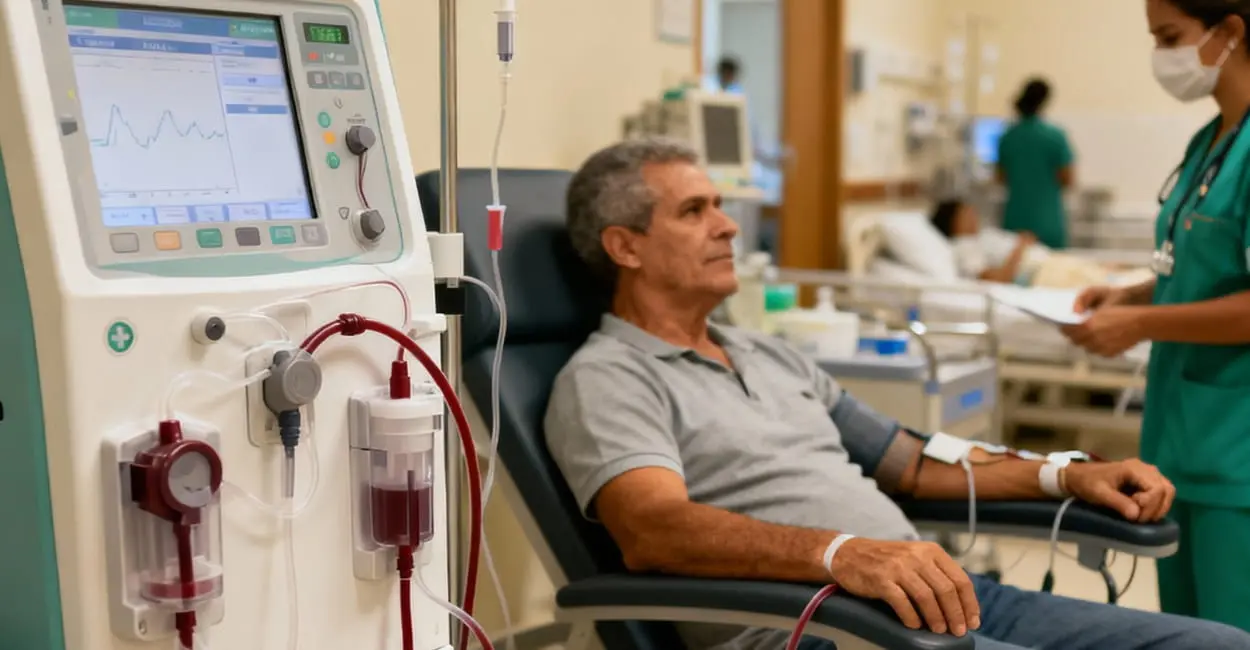

Sim, é possível! Saiba como os avanços da diálise intensificada tornaram o sonho da maternidade real.

Descubra como a hemodiálise e diálise peritoneal substituem a função renal e mantêm a vida.

Entenda como funciona a máquina, o acesso vascular, a rotina das sessões e qualidade de vida.

Entenda em detalhes o processo de filtragem do sangue, o rim artificial e cuidados vitais.